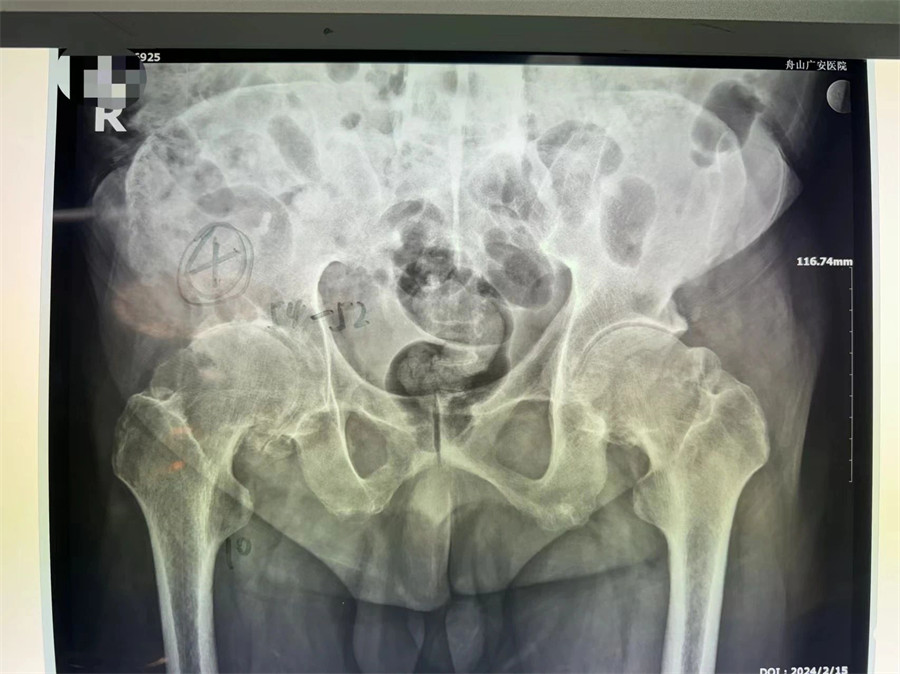

術前拍片顯示髖關節(jié)僵直伴股骨頭壞死

羅軍主任分析患者病情,認為他強直性脊柱炎30年,雙髖關節(jié)強直,骨贅增生嚴重,嚴重影響行走功能,診斷為強直性脊柱炎,雙側(cè)髖關節(jié)骨關節(jié)炎晚期。治療方案只有人工髖關節(jié)置換這一種選擇。因患者的頸腰椎已經(jīng)完全融合,手術和麻醉都是一個不小的挑戰(zhàn),羅軍主任帶領關節(jié)置換團隊協(xié)同麻醉科團隊,經(jīng)過嚴密細致的討論,與患者及家屬充分溝通交流后,決定行機器人輔助DAA入路全髖關節(jié)置換術。機器人輔助加微創(chuàng)置換,為這項高難度手術提供了有力支撐。